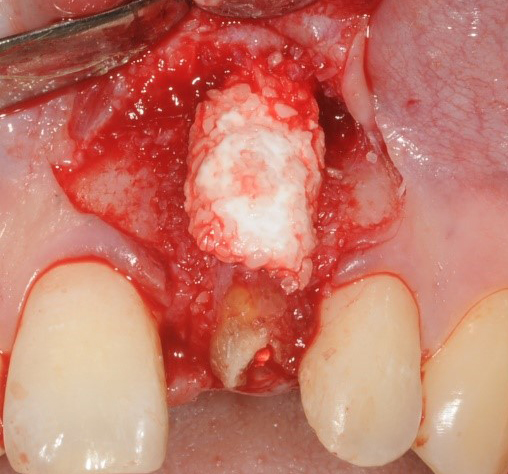

主訴:25歳女性

保母さんで、子供の頭が口にぶつかり、歯が折れて歯肉に腫脹が生じて来院されました。

まだお若い為、治療後は、長期的な予後が求められます。

先に抜歯をすると、頬側の薄い骨が溶けて無くなってしまいます。インプラントを長期的に持たせるには周囲に最低でも2mmの骨の厚みが必要です。

さらに、骨が無くなってしまうことで歯肉が下がってしまうと、審美的にもきれいとは言えません。

このケースは、女性の前歯の治療ですので、特に審美面が美しくあることも要求されます。周りの環境も整えていくために、様々な手順を踏んで治療を行っていきます。

まず、骨の吸収、それに伴う歯肉の退行を防ぐため、根の一部を残し、それを矯正で骨上部まで引っ張りだします。

十分な位置まで根が下がってきたら、骨造りを行い、骨幅を増します。

《インプラント前のGBR(骨造り)の手術》

《GBR(骨造り)前とGBR(骨造り)後》

骨ができたのを確認後、抜歯し、インプラントを埋入しました。